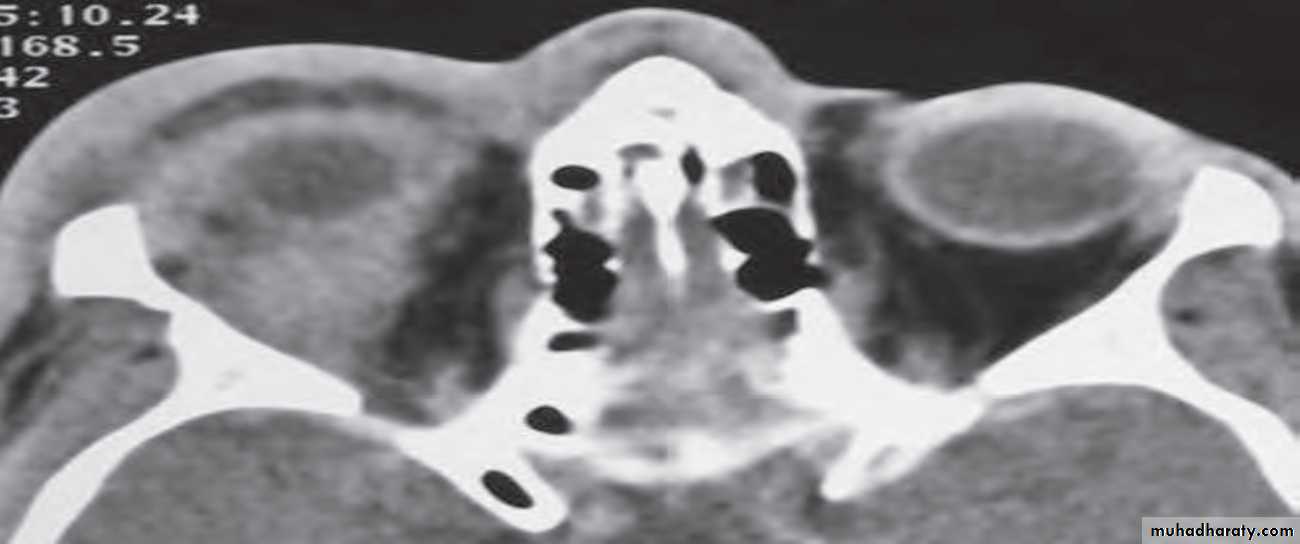

Proptosis